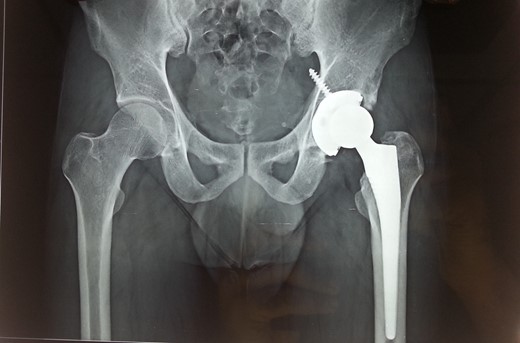

Following trauma patient had left-sided chest pain, frontal headache and severe pain in his left hip region. After hemodynamic stabilization and preliminary treatment for his chest and head injuries, he was evaluated for left hip region pain. Clinically patient had left anterior hip joint line tenderness. Initial X-ray imaging showed impacted subcapital fracture of femur neck, with varus angulation between femur head and neck (Fig. 1), which prompted detailed radiological evaluation. A 3D reconstructed CT scan imaging disclosed a separate fracture line in femur head, with a detached inferior head fragment (Fig. 2); thus, the patient had concurrent ipsilateral fracture of femur head and neck without hip dislocation. We decided to treat this fracture pattern surgically with either osteosynthesis and fixation, or primary total hip arthroplasty. Via posterolateral approach to hip, femur head and neck fractures were exposed. Proximal femur fragment showed severe impaction of cancellous bone, making chances femur head salvage with osteosynthesis precarious. Thus, we performed primary uncemented total hip arthroplasty (Fig. 3). Presently, the patient is 5 years post-surgery without any complaints and ambulates without support or limp.

Recent 5 years follow-up antero-posterior radiograph image of the patient with uncemented total hip arthroplasty prosthesis in situ.